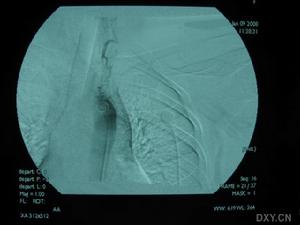

3.腦血管造影有一定的診斷價值71%以上的患者有典型的血管多灶性損害的表現,血管粗細不均,可呈節段性的狹窄或擴張血管阻塞及血管排空延遲等似“臘腸”樣改變,提示腦部血管炎的存在但不能明確是本病的血管炎其他的腦部繼發性血管炎也可有類似的表現有些可因受累的血管太小,腦血管造影可正常

除中樞神經系統症狀外可有發熱、體重下降等全身表現。腦脊液檢查可有細胞數及蛋白的升高,寡克隆區帶陽性。腦活檢可見肉芽腫樣血管炎和/或壞死性血管炎的表現。血管造影可見大腦中小動脈節段性狹窄、擴張及串珠樣改變。1988年Calabrese和Mallek提出了PACNS的診斷標準:①病史和臨床檢查發現原因不明的後天獲得性神經系統損害。②腦血管造影或腦活檢發現有典型血管炎表現。③除外系統性血管炎及其他能引起繼發性中樞神經系統血管炎(血管異常及組織學改變)的各種情況。本例基本皆符合此三條標準。